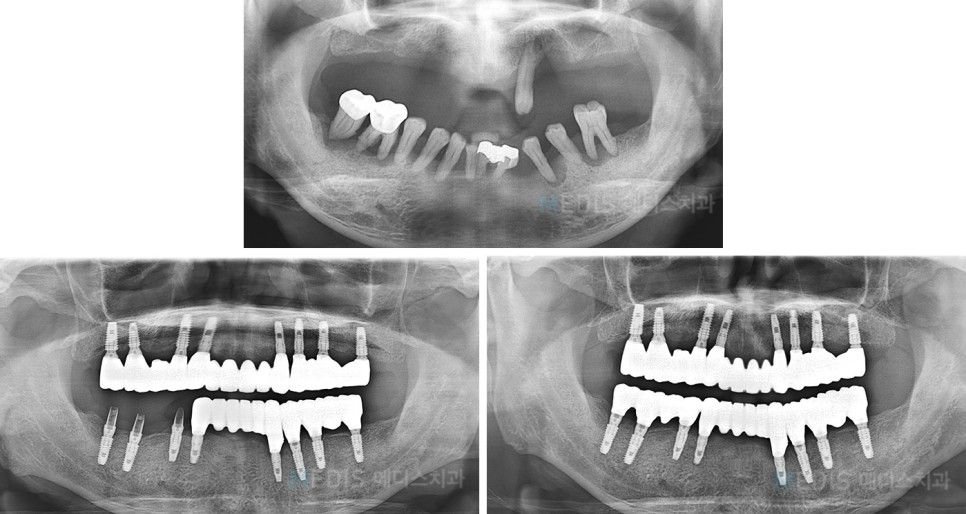

[임플란트] 전체 임플란트 식립 사례

※ 치료기간 : 2016.12.05~2017.09.01

(치료 기간은 환자분의 협조도 이에 따라 달라질 수 있습니다.)

※ 부작용 : 환자의 경향에 따라 통증, 부종과 멍 등의 부작용이 생길 수 있습니다.

*상기 사진은 본원에서 치료를 받은 분의 동의를 얻은 사진으로 실제와 차이가 있을 수 있습니다.

* 상기 사진은 본원에서 동일한 인물이 동일한 조건에서 촬영하였습니다.